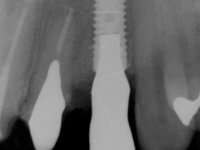

Endodontic treatments were performed and a metalic non screwed intra radicular post was placed on tooth 1.1. An alginate impression was made for laboratory confection of a reinforced acrylic provisional bridge, with teeth 1.1 and 2.2 as abutments and 2.2 as a pontic. After preparation of tooth 1.1 and root preparation of 2.1, the bridge was relined in mouth with self-polymerizable acrylic using a metal post for further retaining the prepared root canal on 2.1. Tooth 2.2 was cut at the gingival level to function as support. In the same session, the impression of the root canal of the 2.1 was made for the laboratory confection of a cast post and core. A double mixture technique with plastic tutor was used after previous canal vaseline with endodontic file and cotton. The provisional bridge was provisionally cemented and the cast post and core was made in the laboratory. Cast post and core cementation was made with resin-reinforced glass ionomer cement and the provisional bridge had to be readjusted to the new situation by removing the post at the site of 2.1. After careful surgical planning, a dental implant was placed, simultaneously with extraction of the root of tooth 2.2. The provisional bridge was placed by resting on the healing screw placed in the implant. The respected osteointegration period was 12 weeks, during which the provisional bridge was relined twice. After complete maturation of hard and soft tissues, definitive impressions were made. The gingival retraction technique was applied with an impregnated retraction cord and impression was performed using double mixture, open tray impression technique. A custom precious metal abutment implant was prepared in the lab, along with 3 metal caps to be used as infrastructures for the metal ceramic crowns. Particular care was taken in the confection of the cervical finishing line of the implant abutment, in order to follow the soft tissues emergence profile. Proof of infrastructures was done in the mouth being evaluated clinically and imagiologically. Collection of color information was done by the ceramist at the office. Ceramic was applied in the laboratory and the finished work was placed in the mouth after approval by the patient. Definitive cementation was made with resin-reinforced glass ionomer cement, and the first crown to be cemented was that of the implant, to facilitate removal of the excess.